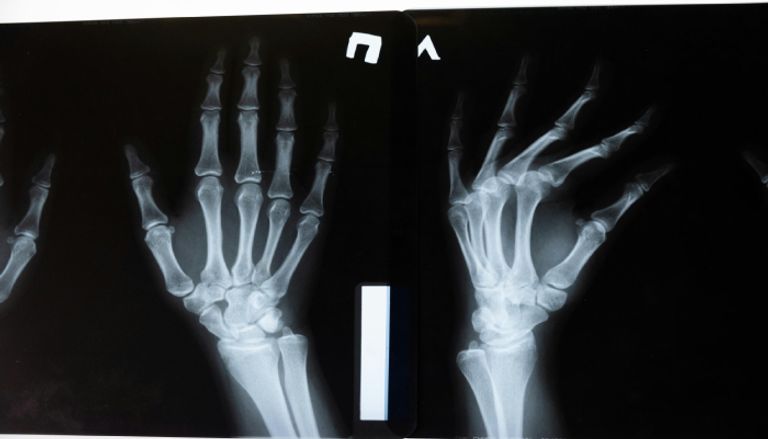

أعلن فريق من الباحثين في مقاطعة تشيجيانغ الواقعة في شرق الصين عن تطوير مادة طبية جديدة عبارة عن "لاصق عظمي" أُطلق عليه اسم Bone-02، قادر على معالجة الكسور وتثبيت الشظايا العظمية خلال ثلاث دقائق فقط، في تقدّم نوعي على مستوى جراحة العظام.

الابتكار، الذي وُصف بأنه نقلة متقدمة في تقنيات تثبيت العظام، قد يشكّل بديلاً عمليًا للزرعات المعدنية التقليدية التي تتطلّب تدخلات جراحية لاحقة.

يتميّز اللاصق الجديد بعدة خصائص رئيسية، أهمها أنه يُمتص بشكل طبيعي من الجسم أثناء عملية الشفاء، مما يُلغي الحاجة إلى استخدام المسامير أو الصفائح المعدنية التي تتطلّب عمليات جراحية لاحقة لإزالتها. وبهذا، يقدّم حلًا يقلل من المضاعفات الجراحية المعتادة، ويختصر فترة التعافي بعد العمليات.